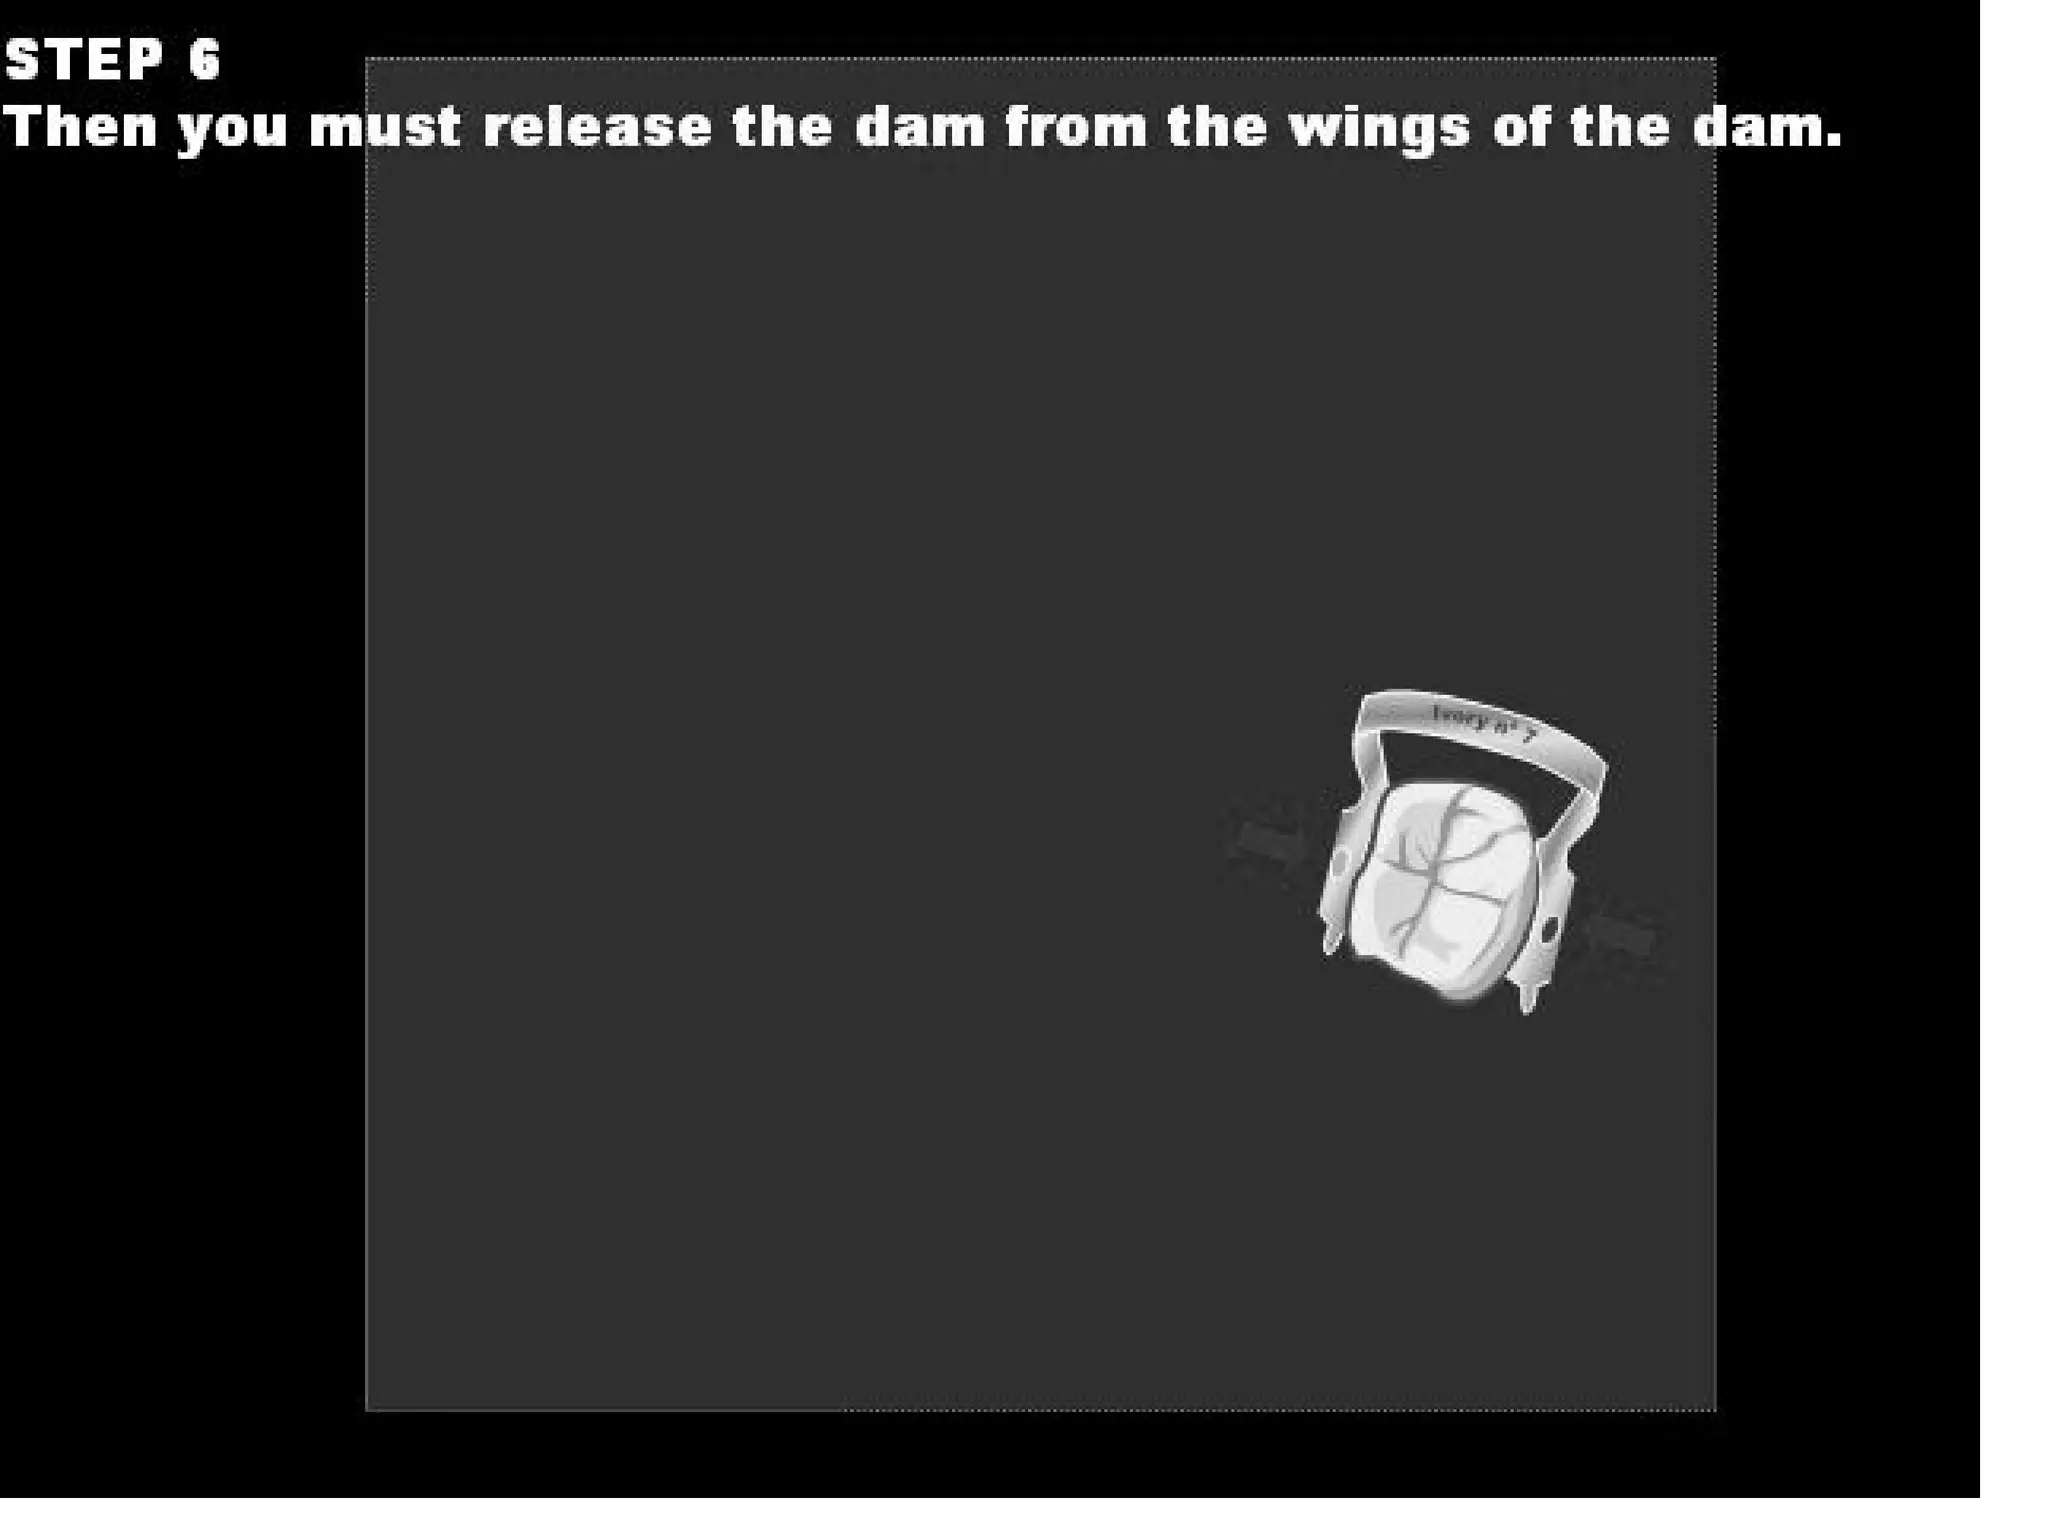

This document discusses the materials and components used for rubber dam isolation in dentistry. It describes the different types of rubber dam materials including color options and napkins to absorb moisture. It also outlines the tools needed such as punches to make holes, templates and stamps to guide hole placement, clamps to secure the dam, and other accessories like wedges and lubricant. Finally, it provides guidance on punching holes for different types of teeth and properly placing clamps in the rubber dam.